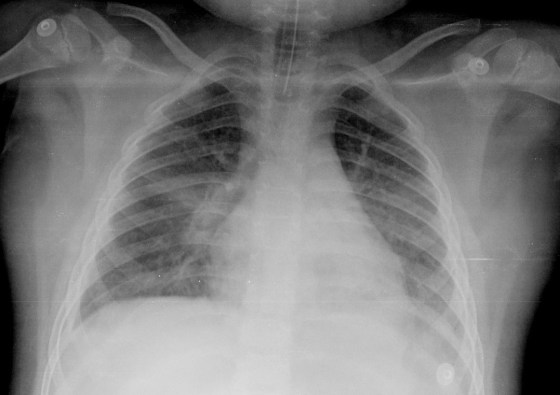

CASO: sospecha de neumonía.

Hallazgos:

- En un principio podríamos decir que existe un aumento de densidad retrocardiaco que podría ser compatible con condensación neumónica a dicho nivel, sin embargo estamos ante una placa poco inspirada, lo cual puede llevarnos a cometer errores diagnósticos.

- Se recomendó volver a realizar la radiografía, observar a continuación:

Ya no se observa el aumento de densidad retrocardiaco, la placa es normal.

INSPIRACIÓN: Una placa bien inspirada es aquella en la que se observar 6-7 arcos costales anteriores o 10-11 arcos costales posteriores. Lo contrario puede producir imágenes falsas de condensaciones o de seudocardiomegalia.